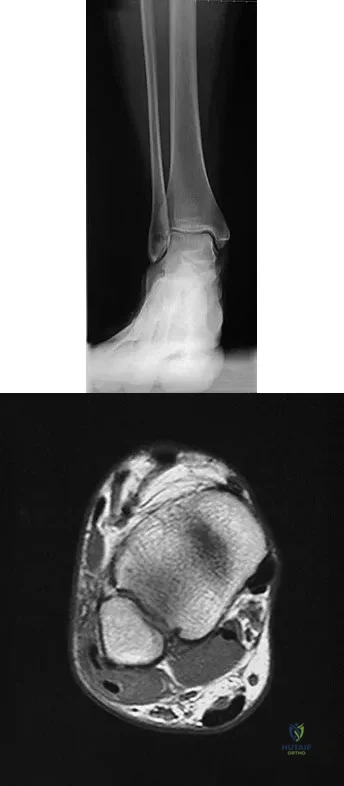

A 25-year-old competitive skier sustains a twisting injury to the right ankle while skiing. She is unable to continue the activity secondary to severe lateral ankle pain. Examination reveals ecchymosis and fullness over the lateral malleolus with pain and weakness on active ankle dorsiflexion and external rotation. There is no medial-sided pain. Neurovascular examination is normal. An AP radiograph and MRI scan are shown in Figures 17a and 17b, respectively. Management should consist of

Explanation